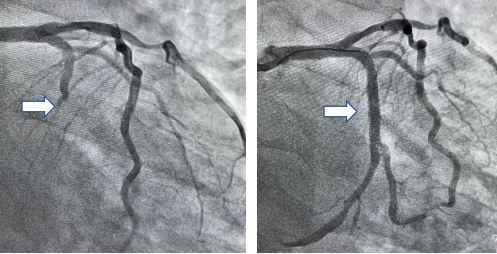

图1 手术直播冠脉造影检查,白色箭头为左回旋支闭塞血管介入处理前后对比

清华长庚医院心脏内科11月8日电(通讯员:薛亚军 张鸥 耿雨) 2021年10月30日,全国抗击新冠疫情的战役仍在紧锣密鼓进行中,北京清华长庚医院心脏内科工作毫不松懈。10月30日18点,我院接诊一例40岁的急性心肌梗死男性患者,急诊冠脉造影显示左回旋支(LCX)中段100%闭塞,并可见血栓影。适逢第32届长城心脏病学暨亚洲长城心脏病学大会2021急诊学术周期间,随后将该病患的资料和病情与线上全国140余位权威专家、160家医院分享,共同探讨急性心梗预防和救治经验。经过与在线专家的充分讨论,对该名患者于梗死相关血管左回旋支成功植入一枚支架,血流恢复TIMI 3级(正常),患者转危为安。